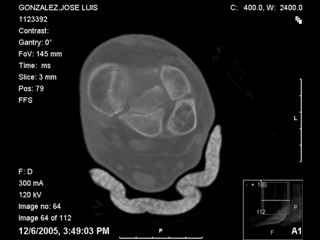

I have attached his x-rays. I have also attached an WMV movie file of his axial CT (if you are unable to view this, I can post an MPEG file).